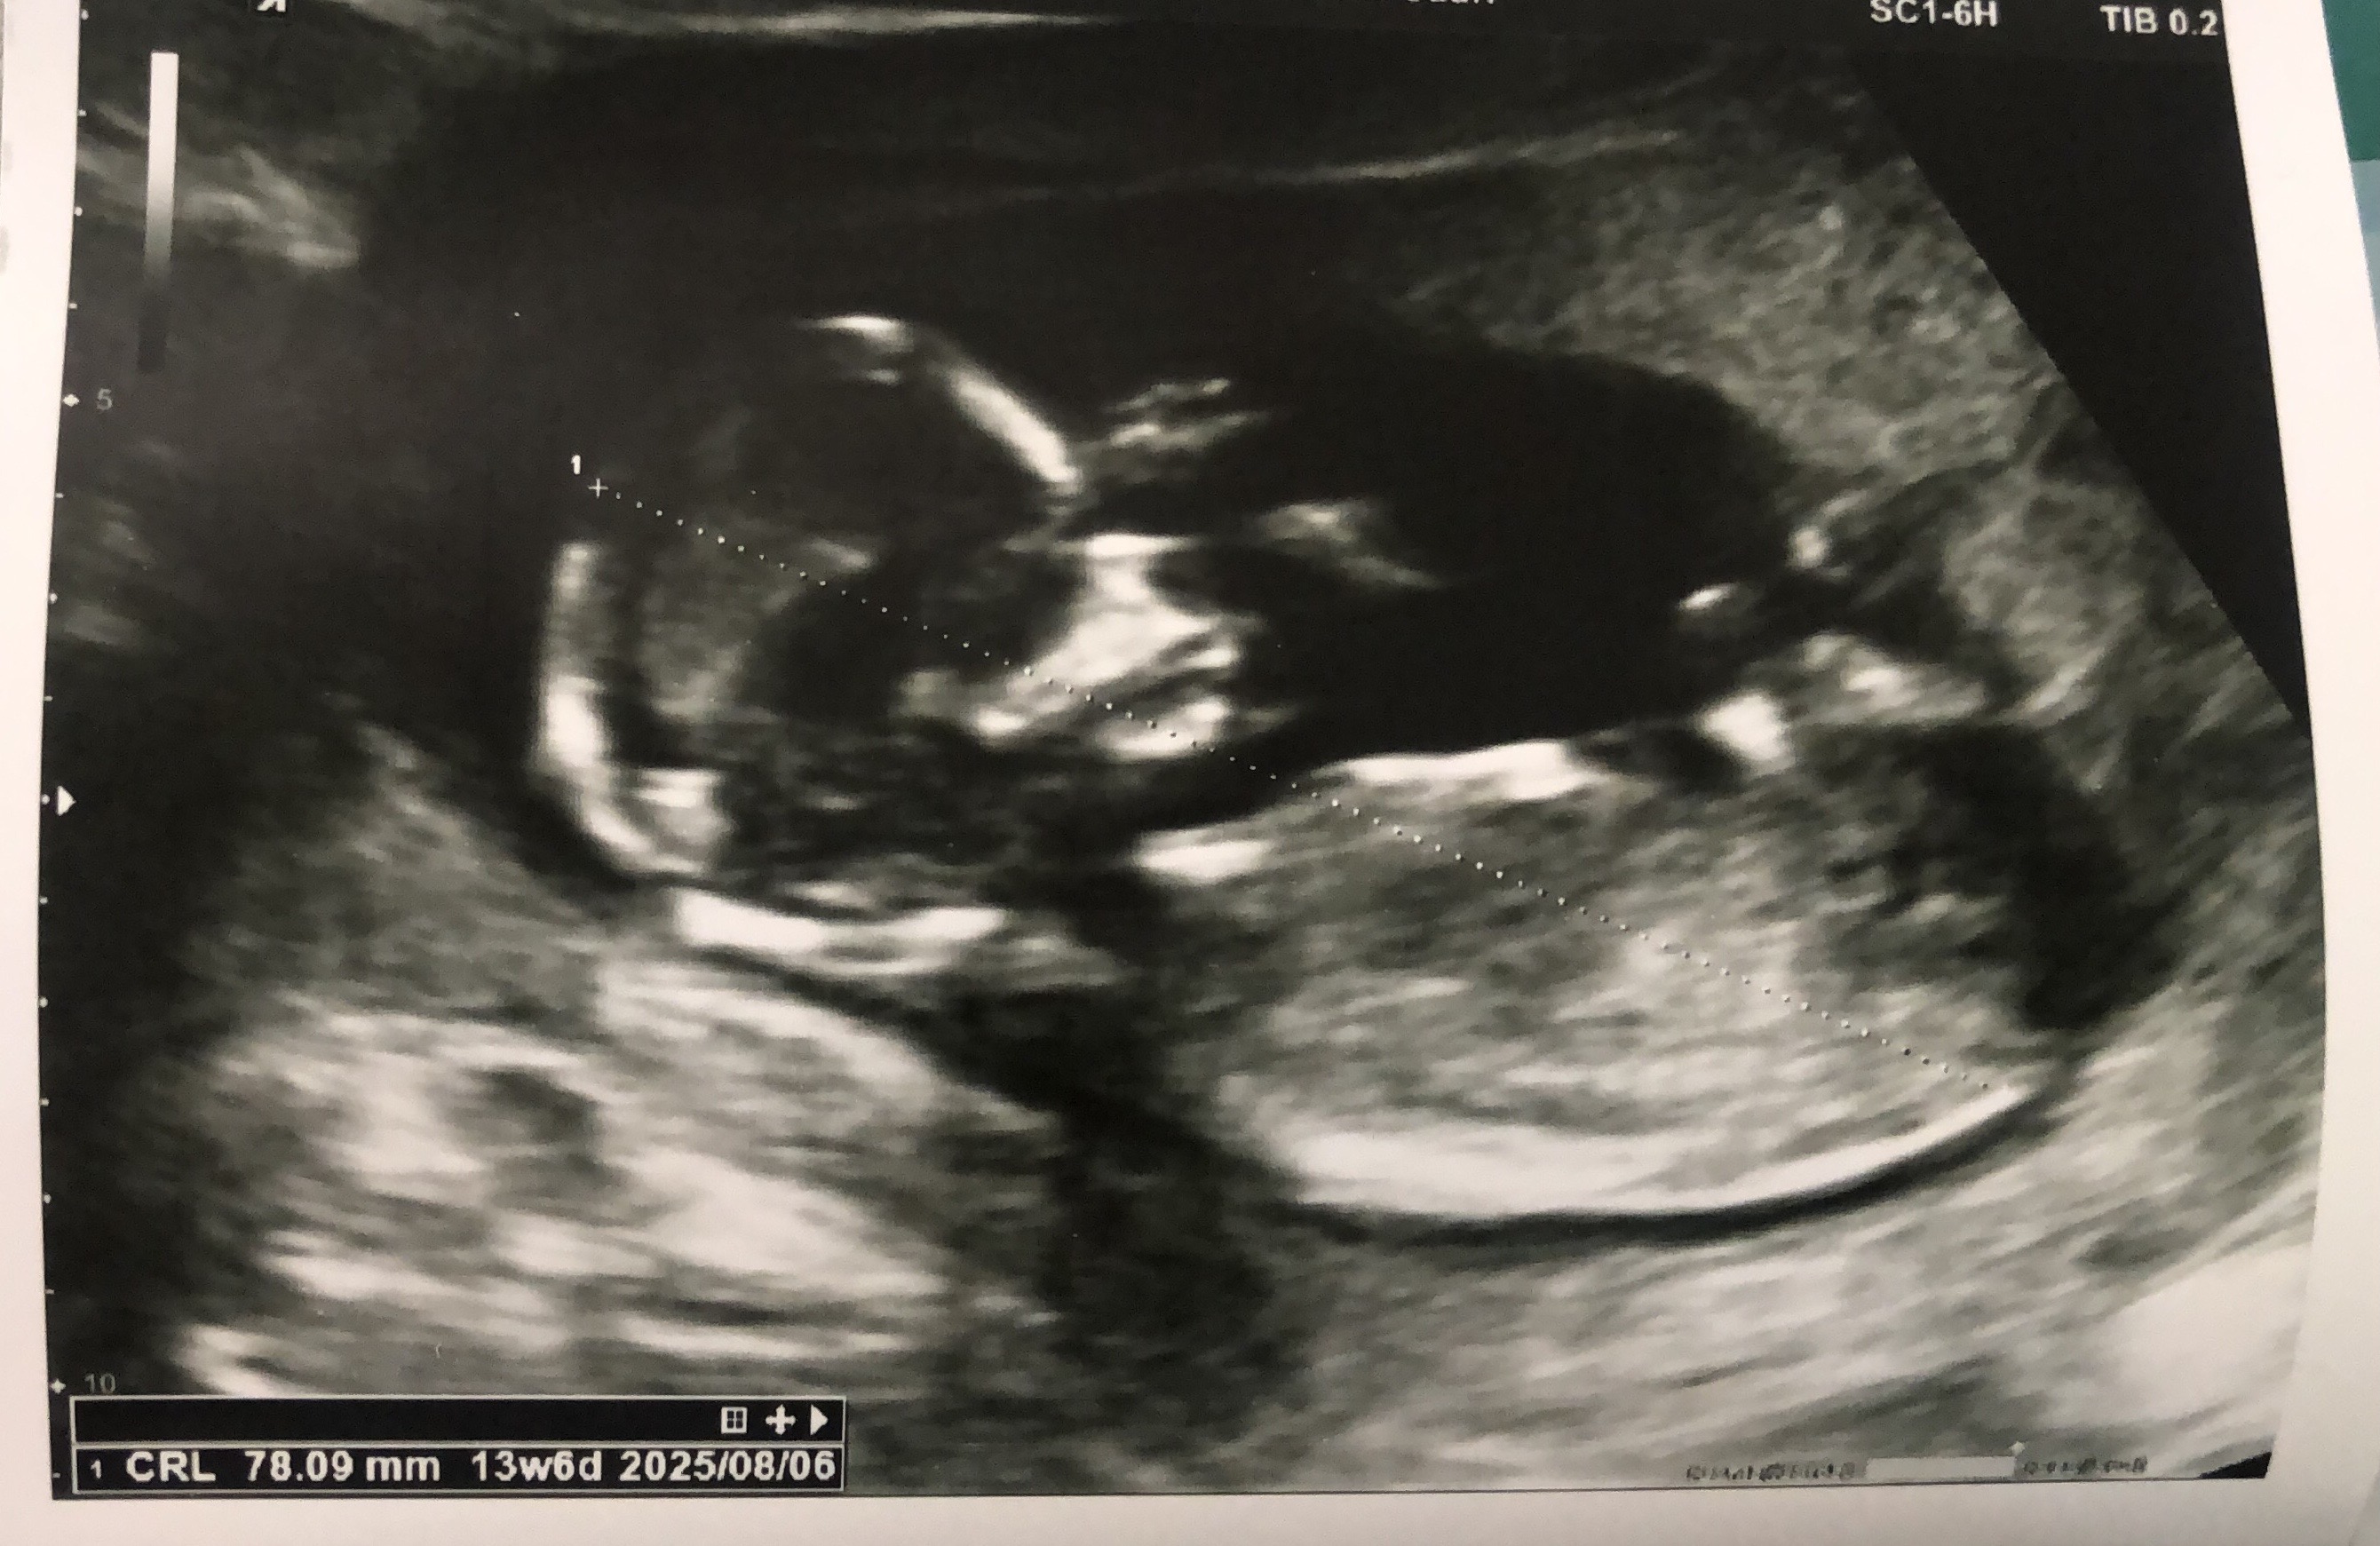

fasin مدیر عضویت: 1397/10/07 تعداد پست: 72 عنوان خانوما بچم جنسیتش چیه | مشاهده متن کامل بحث + 298 بازدید | 34 پست اگه میشه با دلیل بگین ممنون میشم 1403/11/20 | 21:34 0 نفر لایک کرده اند ... گزارش تاپیک نامناسب

fasin مدیر استارتر عضویت: 1397/10/07 تعداد پست: 72 بنظرم نی نیت یه دخمل نازهچون اگه پسر بود ان تی قطعا میگفت زودزاویه فکش هم کشیدست ان تي اصلا جنسيت و نگاه نكرد چون بچه زاويش انقد بد بود كه ان تي شو نميتونست بگيره بعد پرسيدمم گفت نگاه نكردم اندامشو

به_لطافت_گلبرگ عضویت: 1402/06/11 تعداد پست: 4078 ان تي اصلا جنسيت و نگاه نكرد چون بچه زاويش انقد بد بود كه ان تي شو نميتونست بگيره بعد پرسيدمم گفت نگ ... پیشونیش و حالتش بنظره من دختر میاد. سرگرم خودت،عاشق احوال خودت باش🩷

ساغر73 عضویت: 1394/01/29 تعداد پست: 3154 دليلشو ميگي عزيزم؟ پیشونی گردچون خودم 4 تا پسر رو تجربه دارم اینشکلی نبود جمجمه شون هر چی باسه ایشاللا صحیح و سلامت باشه